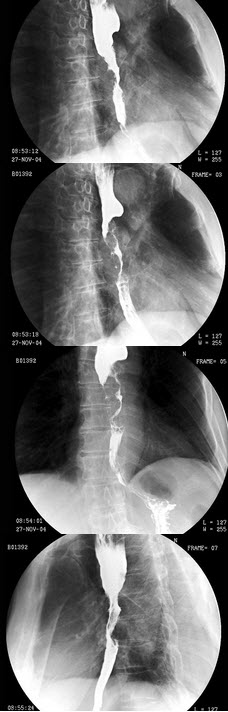

B.狭颈征

男,70岁,进行性吞咽困难半年,结合图像,最可能的诊断为()